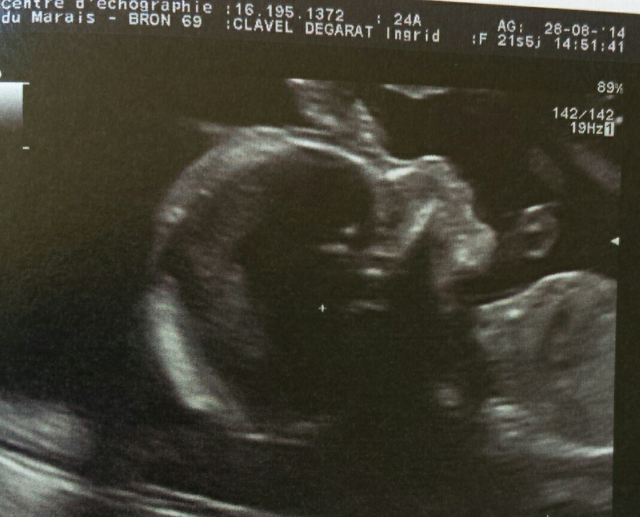

Compte rendu écho:

Pepette bouge beaucoup, coeur ok, mais petit bébé dont diamètre bipariétal juste en dessous de la courbe donc vérifier dans 3 semaines qu'elle pousse bien. Gros flippe au départ et puis on m'a expliqué que pr le moment rien d'inquiétant. On verra dans 3 semaines.